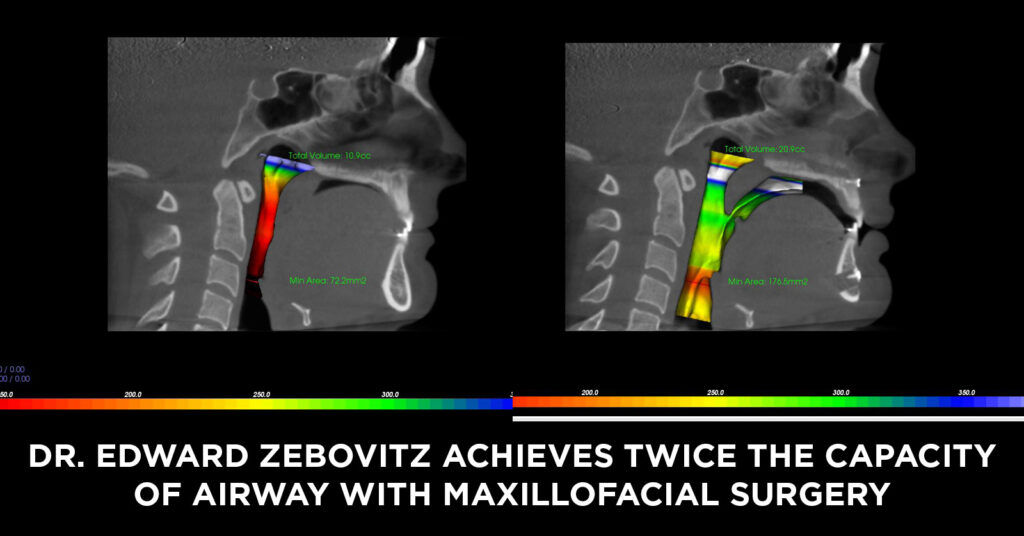

- Sleep apnea (airway obstruction)

- Custom / 3D Bimax / Trimax (usually done at private clinics) : Uses virtual planning and custom titanium plates for perfect symmetry and aesthetic refinement.